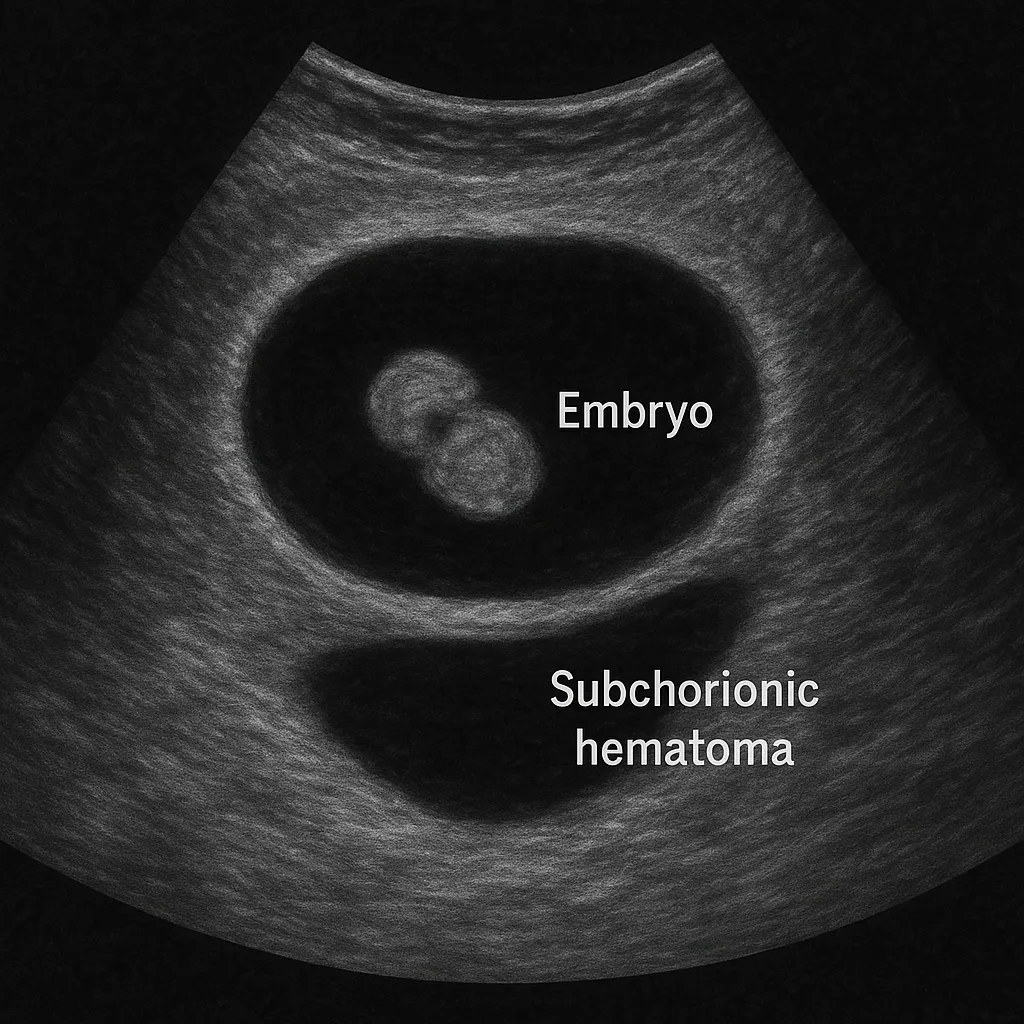

絨毛膜下血腫は、妊娠初期に絨毛膜(胎盤の外側の膜)と子宮内膜の間に血液が溜まる状態を指します。超音波検査で胎嚢周囲に無エコーまたは低エコー像として確認されることが多く、妊娠初期の出血の主な原因の一つです。

| 経腟超音波 | 胎嚢周囲の無エコー~低エコー像 | 最も一般的な診断方法 |